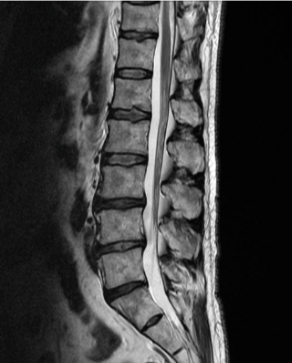

허리디스크 증상 치료방법 및 수술비용에 대해 알아보겠습니다. 허리디스크는 척추 뼈 사이에 있는 디스크가 손상되어 신경을 압박하는 질환입니다. 디스크는 척추뼈 사이의 충격을 흡수하고 척추의 움직임을 부드럽게 해주는 역할을 하는데, 이 디스크가 손상되면 신경을 압박하여 통증, 마비, 감각 이상 등의 증상이 나타납니다. 허리디스크는 흔히 40~50대 중년층에서 발생하지만, 젊은 나이에도 발생할 수 있습니다.

허리디스크의 치료방법은 증상의 심각성과 개인의 상황에 따라 다르게 선택됩니다. 일반적으로는 비수술적 치료가 우선적으로 시도되며, 수술적 치료는 보존적 치료로 증상이 호전되지 않거나 신경마비가 있는 경우에 고려됩니다.

허리디스크는 정확한 진단에 따라 올바른 치료 방법을 선택해야 합니다. 의사와 상의하여 자신에게 가장 적합한 치료 방법을 결정하시